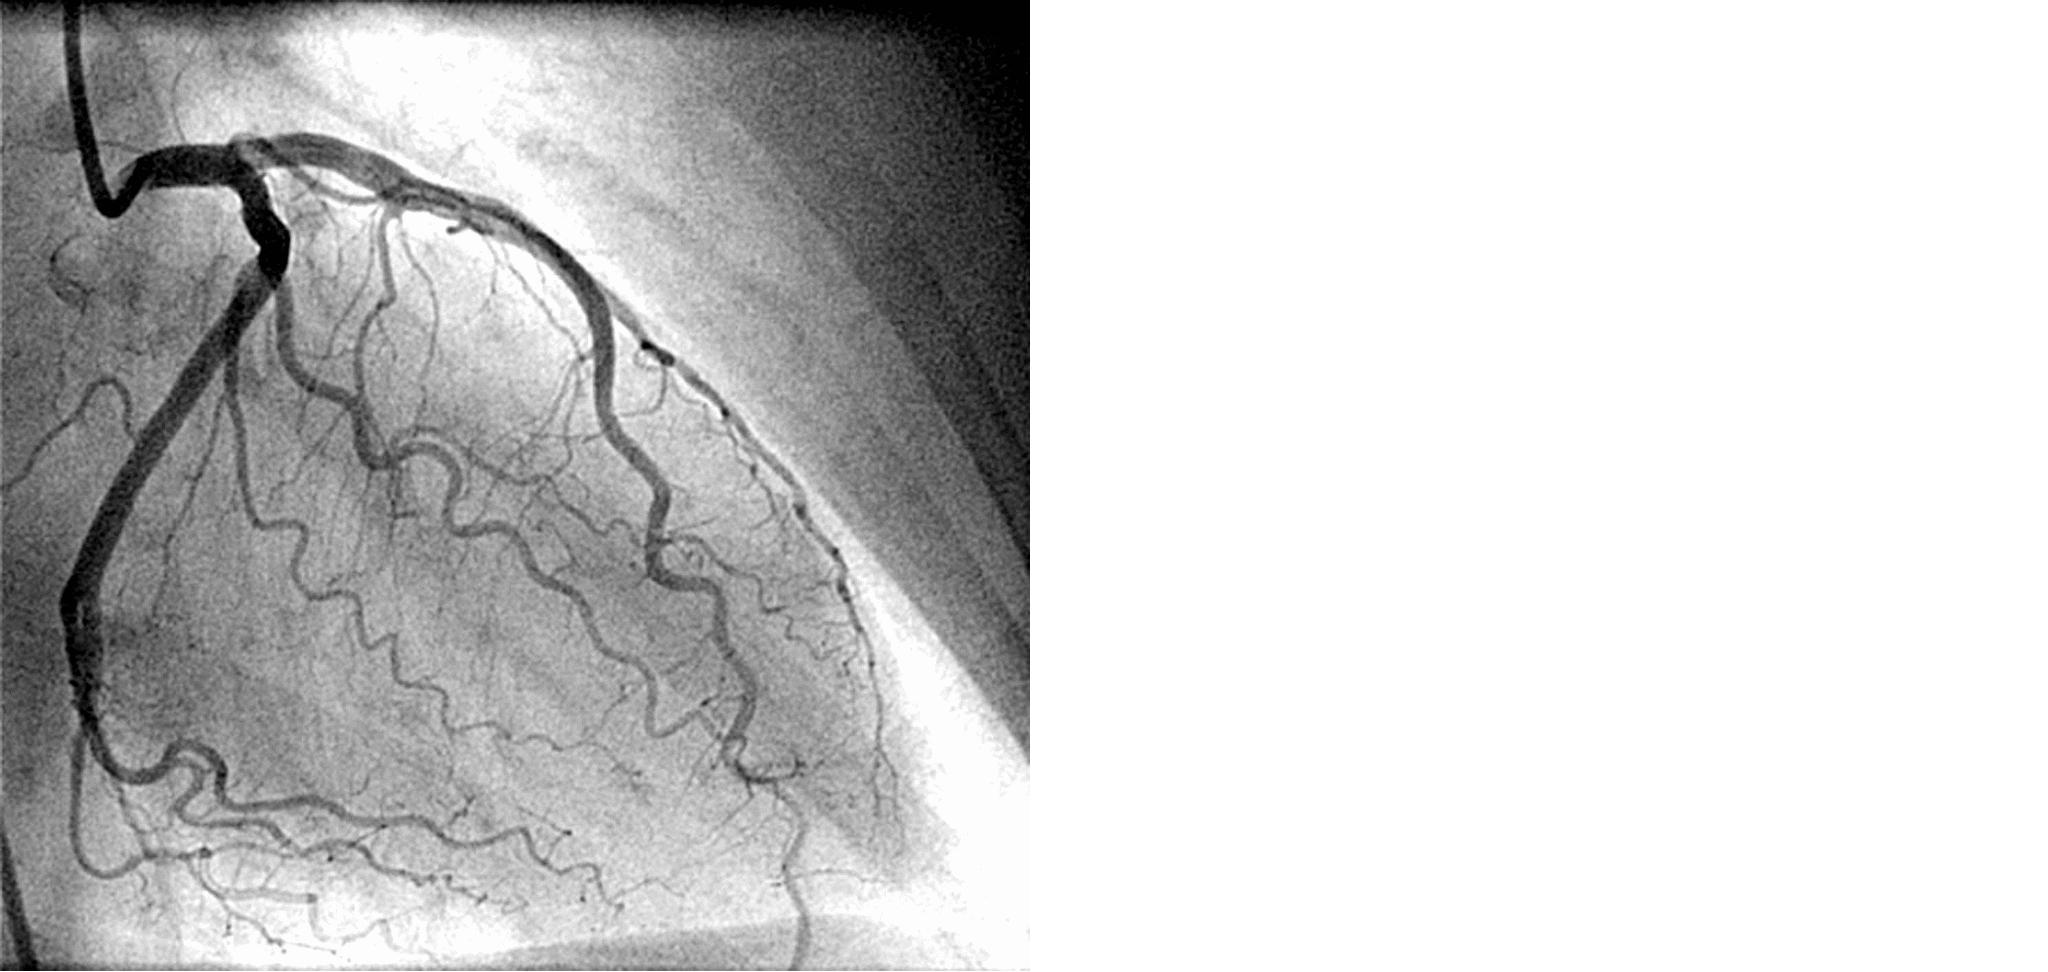

Angiograful INNOVA IGS 540 este aparatura de ultima generatie care foloseste raze X pentru a vizualiza vasele de sânge ale organismului. Radiografiile furnizate de angiografie sunt numite angiograme. Se investighează artere ori vene îngustate, blocate, mărite sau care prezintă malformații din mai multe părți alte corpului: brațe, inimă, gât, piept, picioare.

Angiograful este montat intr o sala hibrida ce permite proceduri minim invazive cu durata scurta de spitalizare.: coronarografii, angiografii vasculare periferice.